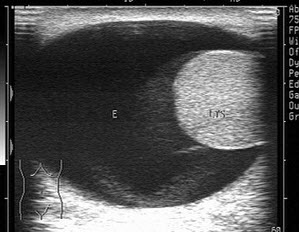

5、单项选择题

某患者脾脏声像图表现如图,诊断为()

A.正常脾脏

B.脾大

C.脾破裂

D.脾梗死

E.以上都不是